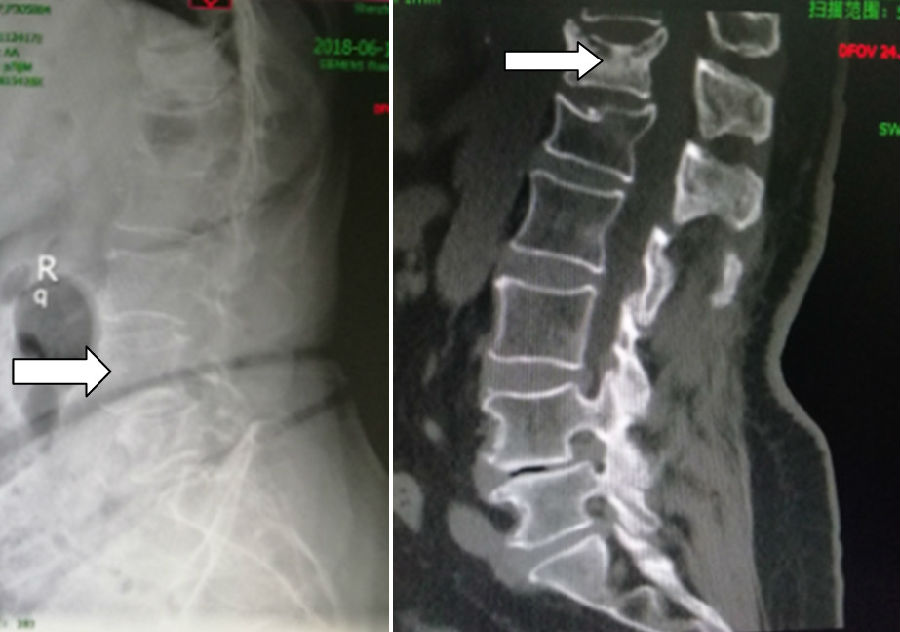

到深圳市中医院办理了住院手续后检查才发现,我的胸12椎体不但有压缩骨折,而且第4腰椎也出现了严重滑脱,导致相应节段神经根长期受牵拉引起双下肢肌力下降,走路困难都是因为它

手术开始,吴老太太全身麻醉后躺在全碳纤维脊柱多功能手术床上,术中运用能够180°自动旋转的“C形臂”透视机器进行三维X线扫描,获得清晰的腰4-5椎弓根的三维图像——手术现场的即时图像。

然后将图像传输到导航系统,就像巡航导弹一样,医生的手术器械放在了患者椎骨的哪个位置都可以清楚地在屏幕上看到。能穿透切口周围50厘米动态视野的红外线发生器接到了暴露的椎体上,并在计算机显示器上显示椎弓根。

何主任通过屏幕看到椎弓根重建图像的准确位置,然后将椎弓根螺钉如“小李飞刀”一般,精准的植入了腰4、腰5椎体内~

吴老太太的案例是深圳市中医院骨伤科在全市中医系统内率先应用术中三维C型臂导航技术进行的“ “腰椎椎弓根内固定术”。三维实时导航,极大地增加了腰椎手术患者的安全性,使得该科椎弓根螺钉植入技术从此迈入零失误率的历史性阶段。